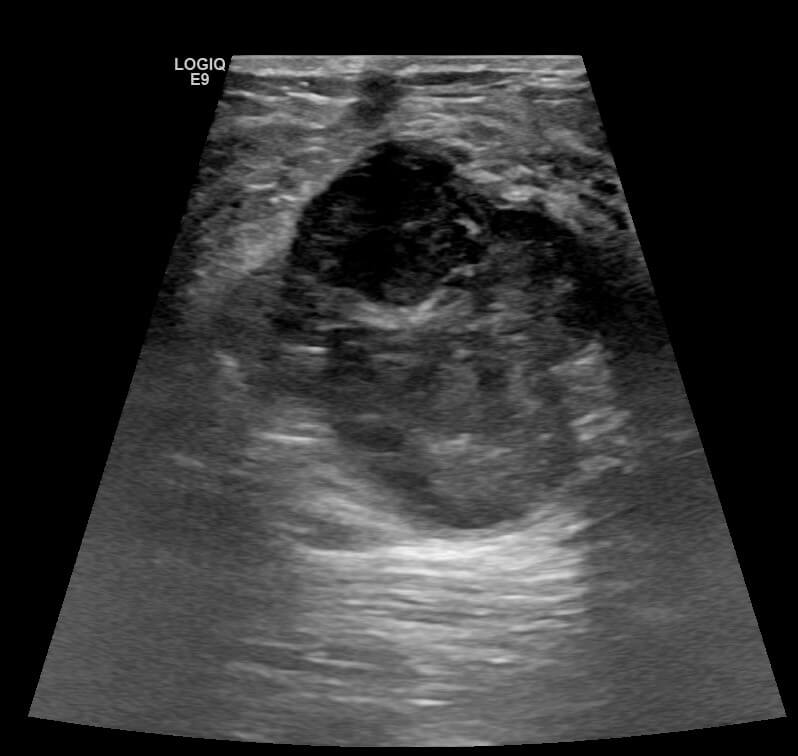

Mammogram revealed the presence of an irregular high density mass in the posterior third of the upper outer quadrant of the right breast with indistinct margins on two-dimensional mammogram. No internal calcification seen. No overlying skin thickening or retraction noted. DBT (Digital breast tomosynthesis) revealed the mass having spiculated margins and irregular shape. Corroborative ultrasound showed an irregular, heteroechoic solid mass at 10-11 O’clock position with anti-parallel orientation, microlobulated margins, posterior enhancement and internal necrotic/ cystic areas within. Mild internal vascularity was seen on color Doppler. No dilated ducts or intraductal extension was seen. No suspicious lymph nodes were present Further recommendation: Ultrasound guided core-needle biopsy with immunohistochemical analysis Management received: Right side lumpectomy with MRM Final histopathology: Metaplastic carcinoma (carcinosarcoma) with no nodal metastasis